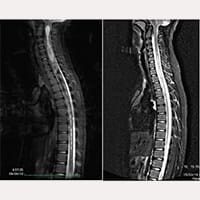

منذ تشرين الأول / أكتوبر 1993 إلى تموز / يوليه 2017، تم علاج أكثر من 1000 مريض مصاب بمتلازمة العصب- الجمجمي-الفقري و/ أو مرض الفيلوم مع أرنولد كياري الأول، تكهف النخاع، والجنف، وفقا لبروتوكولات فيلوم سيستم®. في توليفات تشخيصية مختلفة فيما بينها. في معظم الحالات، تم الحصول على نتائج إيجابية ارتفاع في معدل رضا المرضى